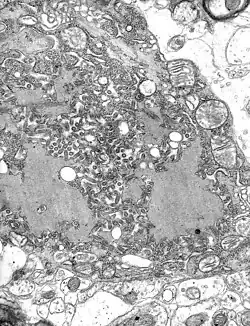

Foto gemaakt middels TEM met talrijke rabiesvirionen (kleine, donkergrijze, staafvormige deeltjes) en Negri-lichaampjes (de grotere pathognomonische cellulaire insluitsels van rabiesvirus)

Het rabiësvirus is de typesoort van het genus Lyssavirus, in de familie Rhabdoviridae, orde Mononegavirales. Lyssavirussen hebben een helixvormige symmetrische structuur, met een lengte van ongeveer 180 nm en een doorsnede van ongeveer 75 nm.[4] Deze virussen hebben een envelop en zijn RNA virussen met een genoom van enkelstrengs RNA in negatieve (omgekeerde) richting (sense). Het genetische materiaal is verpakt als ribonucleoproteïnecomplex waarin RNA stevig is gebonden door het virale nucleoproteïne. Het RNA-genoom van het virus bevat vijf genen waarvan de volgorde zeer geconserveerd is: nucleoproteïne (N), fosfoproteïne (P), matrixproteïne (M), glycoproteïne (G) en het virale RNA-polymerase (L).[5]